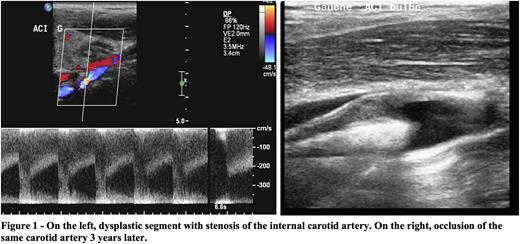

Among 81 patients with extracranial internal carotid lesions and no ipsilateral intracranial vasculopathy, 39 had brain lesions on MRI, which were territorial infarcts in 21. Five patients had an ischemic stroke during a 47 months follow-up including 2 due to the initial cervical artery lesion. One of them is illustrated in Figure 1.